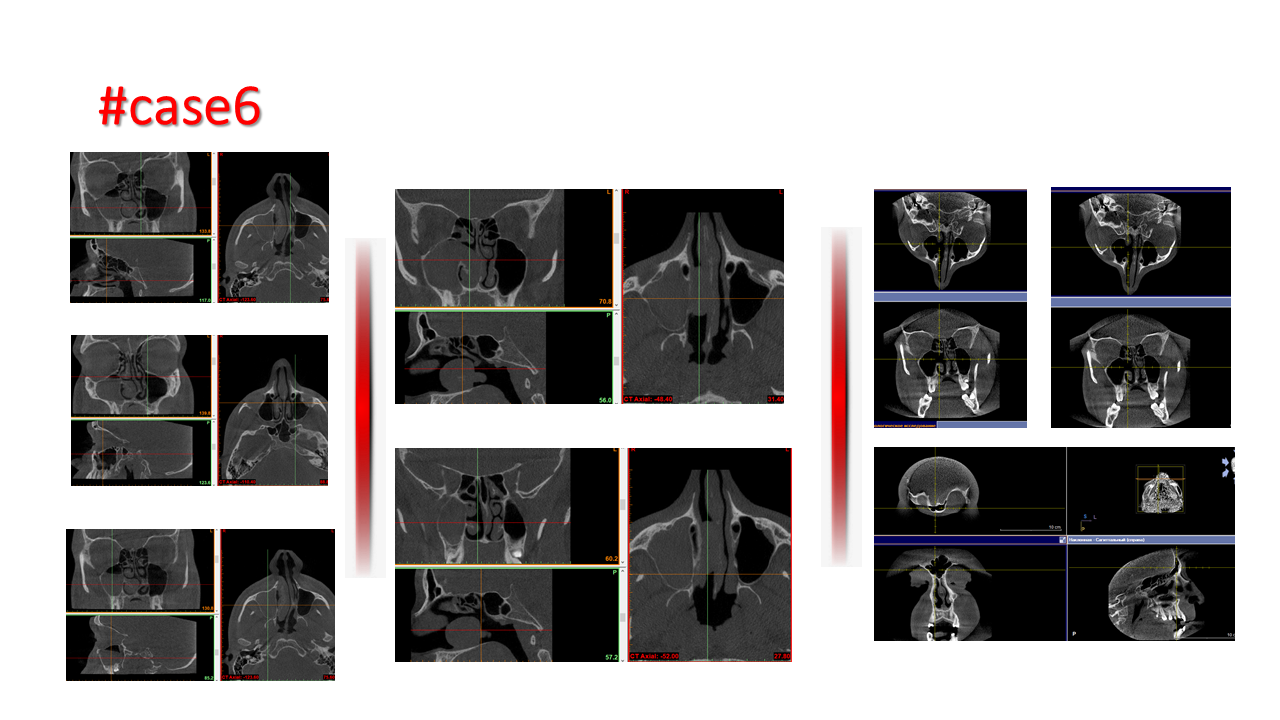

FESS Case Review and Radiologic Analysis (30.09.2016)

Case-based presentation focused on pre- and postoperative imaging in functional endoscopic sinus surgery (FESS). Includes anatomical landmarks, surgical variations, sinus pathology, and technique evaluation. Delivered by Dr. Levon Galstyan at AAOMFS.